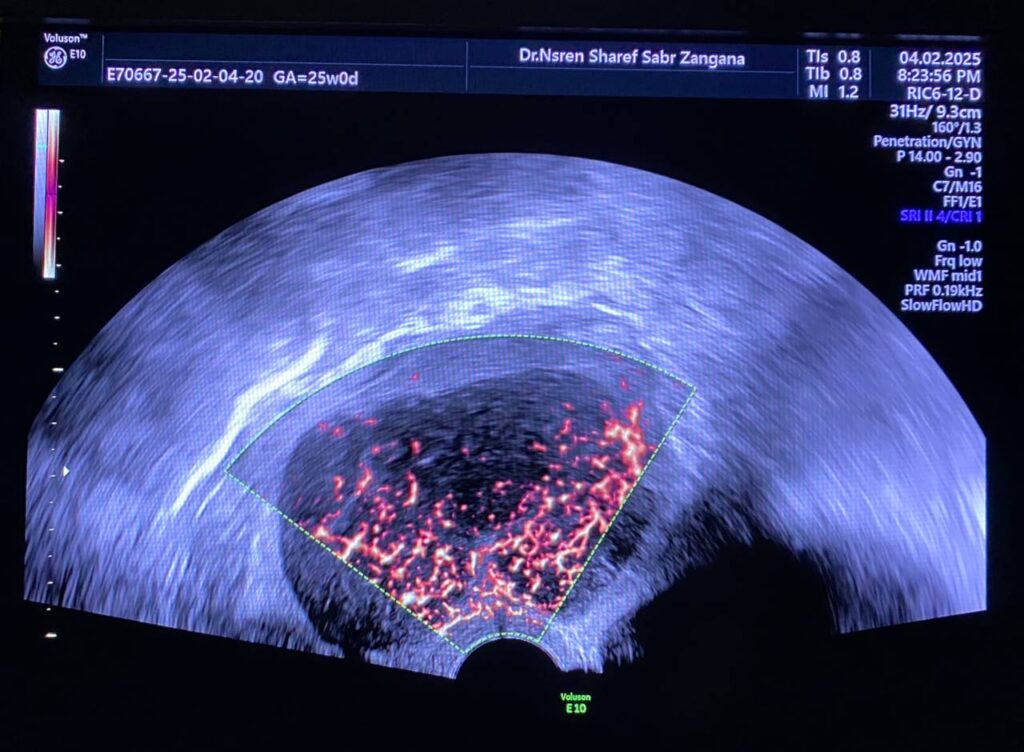

Bulky uterus, endometrial lining thickness 2mm, occupied by clear avascular fluid , mostly due to mass effect , Presence of hypoechoic solid mass 68x48mm ,vascular on color Doppler , Color Score 4 (Hyper vascular) , within right sided posterior submucosal subserosal region , associated with other two smaller masses seen on the anterior wall , their sizes are 19x18mm& 8x12mm (Metastasis? Lymphoma ??) or other suspicious masses

Associated with Presence of pathological lymph node in the right para iliac region size 35x24mm& other pathological lymph node in the left para iliac region 35x21mm , lymphoma or secondary metastasis can not be excluded

Atrophied both ovaries, bilateral few tiny follicles, their sizes less than 2mm, no dominate follicle, nor mass

No free pelvic fluid